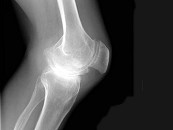

- 单项选择题男,38岁, 左膝痛,受伤时出血较多, 结合图像,最可能的诊断是 ( )

A、白血病

B、血友病性关节炎

C、骨巨细胞瘤

D、退行性骨关节病

E、类风湿关节炎